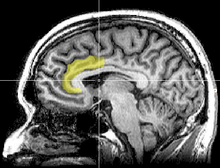

Anterior cingulate cortex (ACC):大脑前额叶 的 内侧前扣带回

彭凯平:“信念固执”的人大脑前额叶的内侧前扣带回发育有问题,灰质容量比较小,无法处理复杂的矛盾信息,但这只是意味着他们更容易产生“信念固执”的倾向,并非一定会“信念固执”;更何况,有的人的“信念固执”是装出来的。

Wikipedia [Anterior cingulate cortex]:

Studying the effects of damage to the ACC provides insights into the type of functions it serves in the intact brain. Behavior that is associated with lesions in the ACC includes: inability to detect errors, severe difficulty with resolving stimulus conflict in a Stroop task, emotional instability, inattention, and akinetic mutism